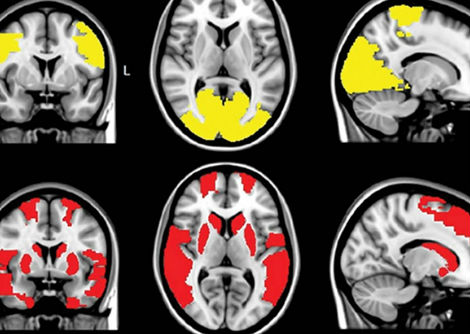

درس الباحثون نوعين من الخلايا العصبية في دماغ الفأر:

• خلايا AgRP العصبية الموجودة في النواة المقوسة تحت المهاد (hypothalamus)، وهي المسؤولة عن تحفيز الإحساس بالجوع.

• خلايا PVH العصبية الموجودة في النواة المجاورة للبطين تحت المهاد، وهي تساعد في كبح الجوع.

تتفاعل هاتان المجموعتان من الخلايا العصبية بشكل وثيق. ففي الظروف الطبيعية، ترسل خلايا AgRP إشارات مثبطة إلى خلايا PVH، ما يؤدي إلى الإحساس بالجوع. وعندما تُثبَّط خلايا AgRP، تصبح خلايا PVH أكثر نشاطًا، مما يقلل الشهية.

وجد الفريق البحثي أن لاك-في يعمل مباشرة على خلايا AgRP ويثبط نشاطها، مما يسمح لخلايا PVH بأن تصبح أكثر نشاطًا، وبالتالي يقل تناول الفئران للطعام. والأهم أن سلوك الفئران العام لم يتأثر، مما يشير إلى أن لاك-في يقلل الشهية دون آثار جانبية سلبية.